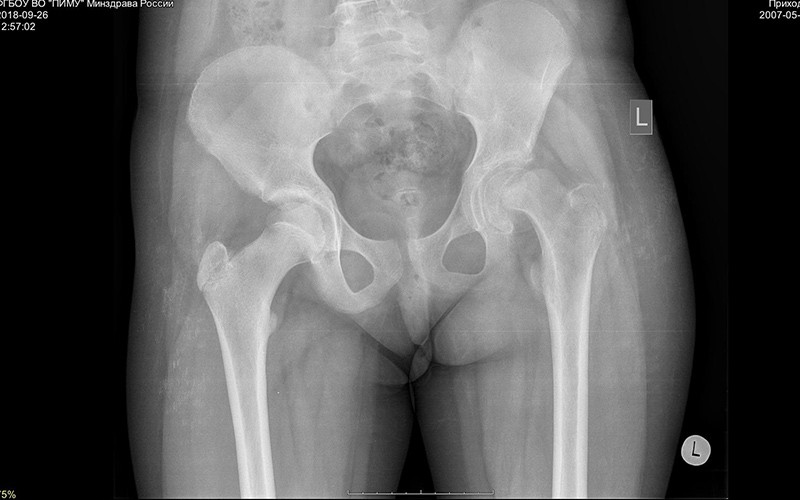

Дисплазия тазобедренного сустава у детей: причины, симптомы и лечение

Узнайте, что такое дисплазия тазобедренного сустава у детей, какие симптомы указывают на патологию, как проводится диагностика и какие методы лечения наиболее эффективны